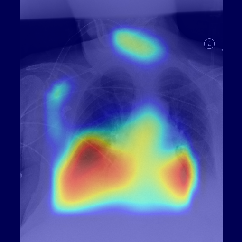

Fig.Β 5: Examples of class activation maps of positive cases. Left to right: image with annotation in blue, no L1 regularization, with L1 regularization, baseline.

Fig. 5 shows examples of class activation maps of positive cases for visual comparisons among the final models. These were produced using the Grad-CAM approach [14]. The images were annotated by an expert for the regions of opacity. Although all models correctly classified the cases as positives, the activation maps of the baseline model were barely correlated with the annotated regions, with more irrelevant hot spots outside the lungs. On the other hand, the activation maps of the models with feature selections were better correlated with the annotation. In other words, these smaller networks seems to be also more focused on the correct regions, which is a step towards explainability. The image in the third row shows that the VGG16 activation map has important components outside the lungs, focusing on English characters on the image. Whereas the reduced networks show more activation in marked areas of the lungs.